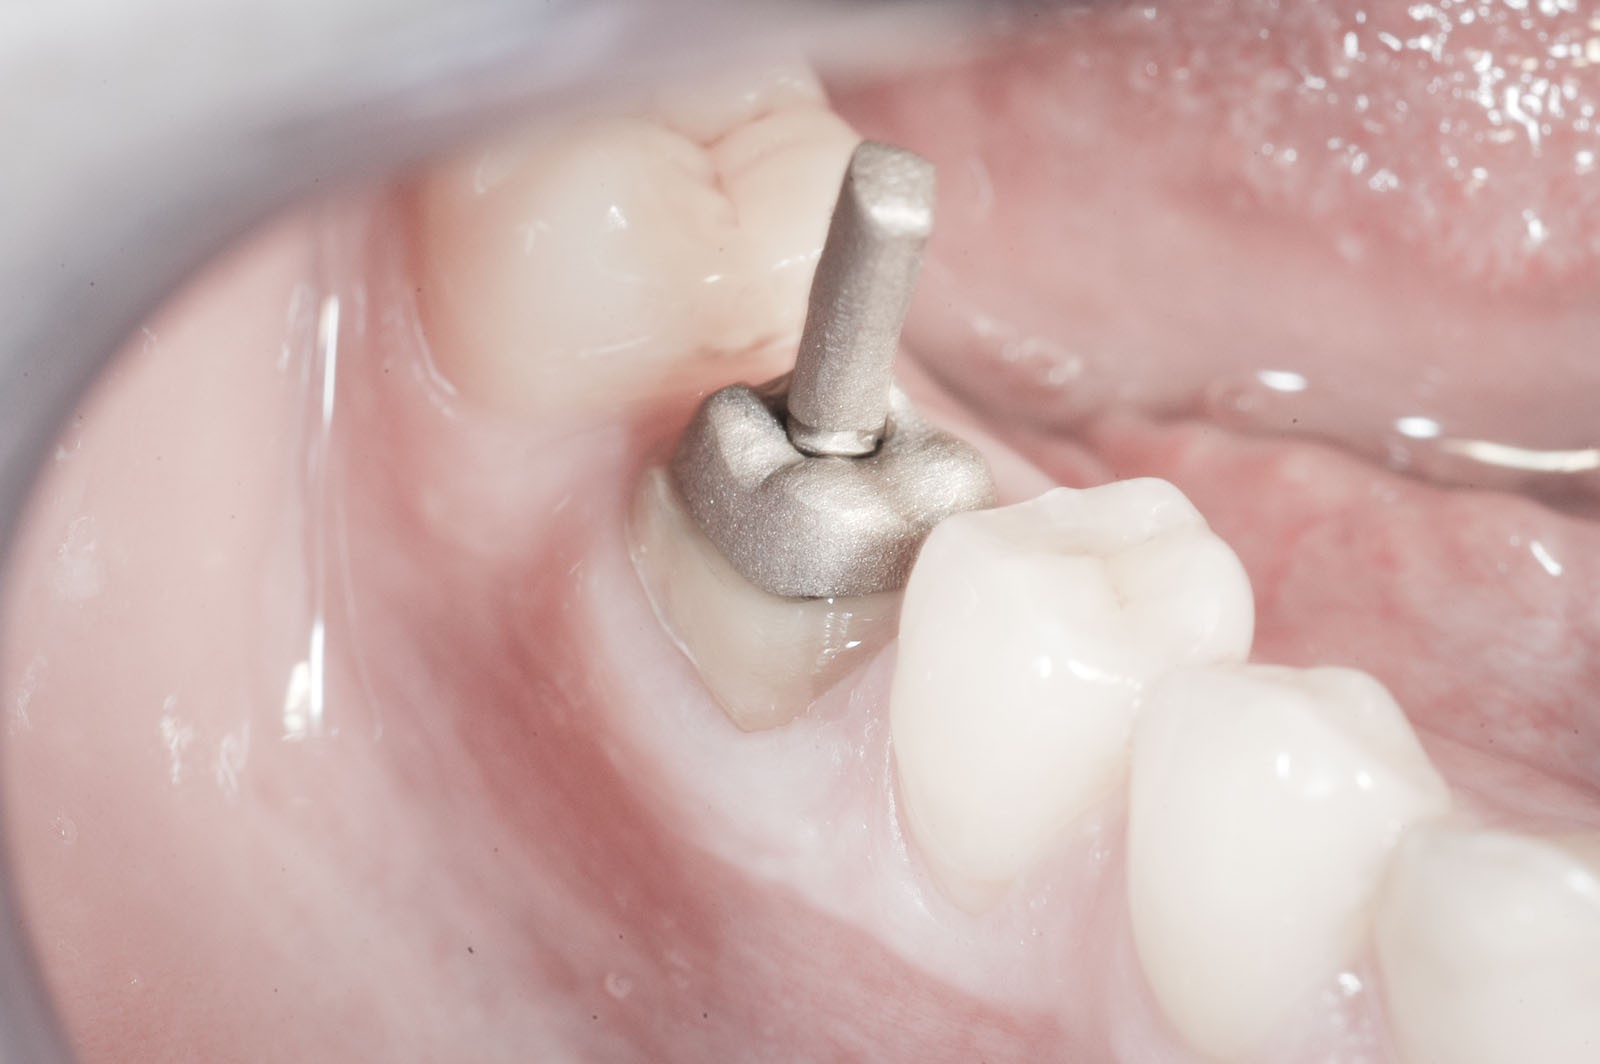

Korona protetyczna ma za zadanie odbudować zniszczoną część naddziąsłową pojedynczego zęba. Przy dużej destrukcji twardych struktur zębowych często wykonanie korony powiązane jest z leczeniem endodontycznym. W sytuacji dużych zniszczeń części koronowej zęba i słabej retencji dla przyszłej korony protetycznej dodatkowo ząb powinien zostać wzmocniony wkładem koronowo-korzeniowym indywidualnie odlewanym ze stopów metalu w laboratorium lub gotowym, wykonanym z włókna szklanego. Wkład koronowo-korzeniowy cementuje się w kanale korzeniowym po prawidłowo przeprowadzonym leczeniu kanałowym.

Wkłady koronowo-korzeniowe to rusztowanie dla korony zęba. Ich zadaniem jest jego wzmocnienie. Stosuje się je w zębach leczonych kanałowo, w których doszło do dużego zniszczenia struktur korony zęba.

Wskazaniem do wykonania wkładów koronowo-korzeniowych jest wzmocnienie zęba leczonego kanałowo, w którym doszło do powstania dużego ubytku w jego części koronowej. Jeżeli ząb ma niewiele tkanek własnych lub są one uszkodzone, grozi to powstaniem naprężeń, w wyniku których może dojść do odłamania się jego ścian. Wkłady koronowo-korzeniowe zapobiegają uszkodzeniom mechanicznym zębów.

Komfortową alternatywą dla mostu jest rehabilitacja implanto-protetyczna, zarówno w przypadku braku pojedynczego, jak i większej liczby zębów. Implantacja wskazana jest w szczególności, gdy zęby sąsiadujące z luką są zdrowe, nie leczone kanałowo, a podłoże kostne spełnia warunki dla implantacji. Pozwala to uniknąć szlifowania zębów filarowych stojących obok luki, a przyszła konstrukcja protetyczna najczęściej nie uwzględnia przęsła mostu, które może sprawiać trudności w utrzymaniu higieny jamy ustnej. Korony i mosty wsparte na implantach przenoszą siły powstające w procesie żucia przez osie implantów wszczepionych w kość. Tworzy to układ działania sił najbardziej zbliżony do fizjologicznych warunków jamy ustnej z uzębieniem. Jest on optymalny dla zdrowia i zachowania tkanki kostnej. W ten sposób przenoszona siła powoduje wzmocnienie kości, nie zaś jej resorpcję, czyli zanik.